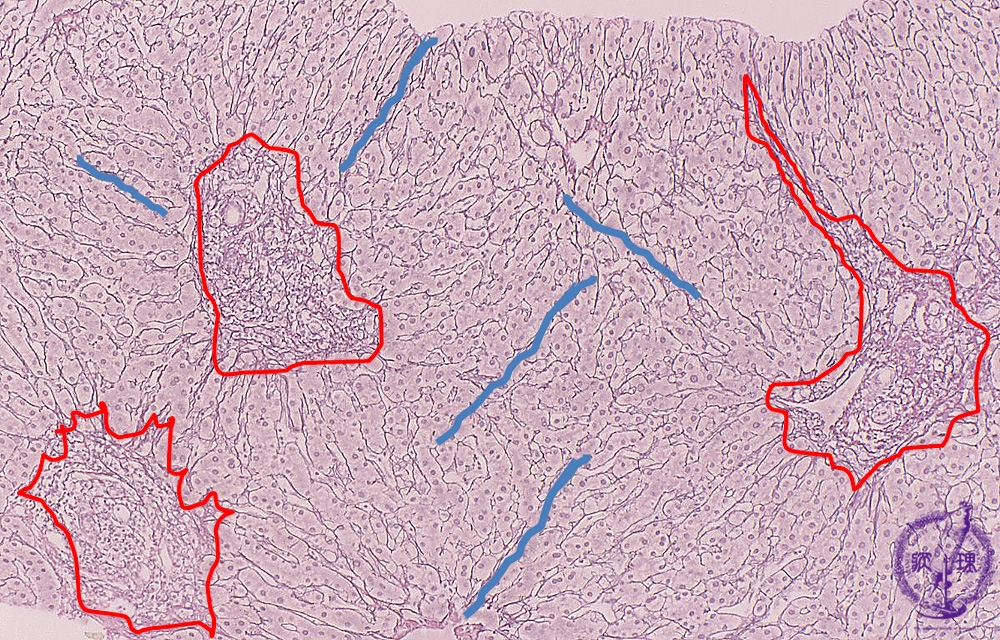

Microscopic image (silver stain, intermediate-power): There is portal fibrous expansion (red box) with varying degrees of bridging fibrosis (blue line).